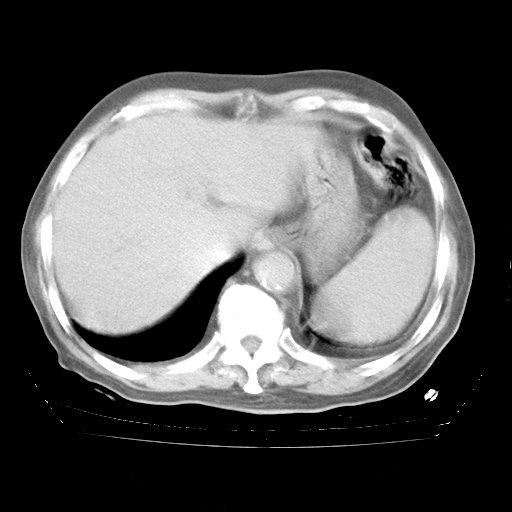

4月28日肺部CT——再次出现类似去年5月9日——透光度降低,“间质性”改变。

4月28日肺部CT——再次出现类似去年5月9日——磨玻璃样、间有“粟粒样”改变。

4月28日肺部CT